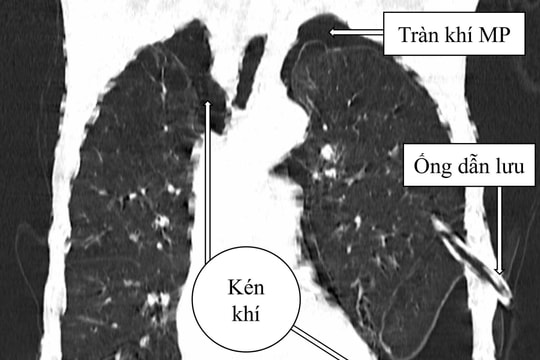

Bệnh viện Đa khoa Trung ương Quảng Nam điều trị thành công ca tràn khí màng phổi phức tạp

ĐNO - Bệnh viện Đa khoa Trung ương Quảng Nam vừa điều trị thành công một trường hợp tràn khí màng phổi phức tạp do kén khí vỡ.